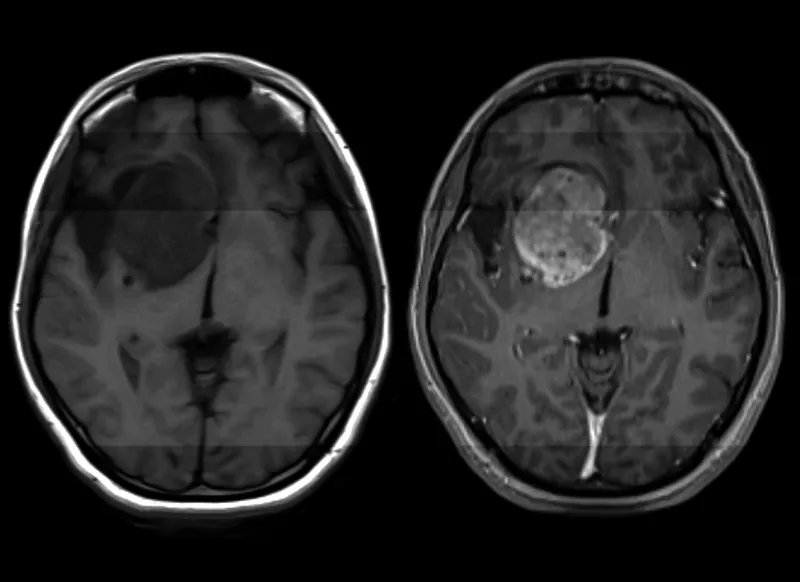

Ας μια άκρως πολύ σημαντική εξέλιξη όσον αφορά την παθολογία του γλιοβλαστώματος, ένας από τους πιο συχνούς καρκίνους του εγκεφάλου για τον οποίο αυτή τη στιγμή δεν υπάρχει κάποιου είδους θεραπεία. Ερευνητές σε επιστημονική δημοσίευσή τους στο Science Translational Medicine, αναφέρουν ότι κατάφεραν να βρουν τρόπο να τον καταπολεμήσουν.

Σύμφωνα με στοιχεία, κάθε χρόνο περισσότεροι από 14.000 άνθρωποι στις ΗΠΑ διαγιγνώσκονται με γλοιοβλάστωμα, ένας επιθετικός, απρόβλεπτος και χωρίς δυνατότητα πρόληψης καρκίνος στον εγκέφαλο.

Καθένας από αυτούς τους νέους ασθενείς στους οποίους γίνεται διάγνωση του εν λόγω καρκίνου θα ζήσει κατά μέσο όρο για 12 με 18 μήνες χωρίς να υπάρχει κάποια θεραπεία και μόλις μία στις 20 περιπτώσεις θα καταφέρει να παραμείνει εν ζωή μετά από 5 έτη.